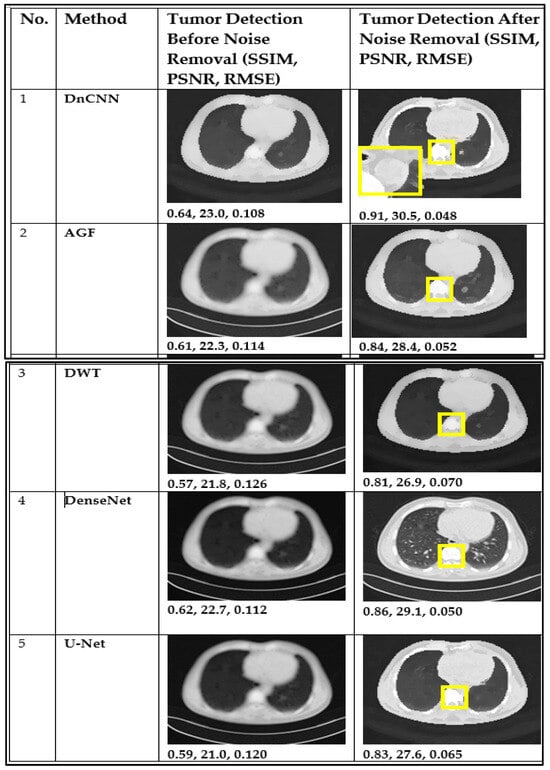

| 1 | DnCNN | 0.64 | 0.91 | 23.0 | 29.5 | 0.108 | 0.048 |

| 2 | AGF | 0.61 | 0.84 | 22.3 | 28.4 | 0.114 | 0.052 |

| 3 | U-Net | 0.60 | 0.83 | 22.0 | 27.6 | 0.120 | 0.065 |

| 4 | DWT | 0.57 | 0.81 | 21.8 | 26.9 | 0.126 | 0.070 |

| 5 | DenseNet | 0.62 | 0.86 | 22.7 | 29.1 | 0.112 | 0.050 |